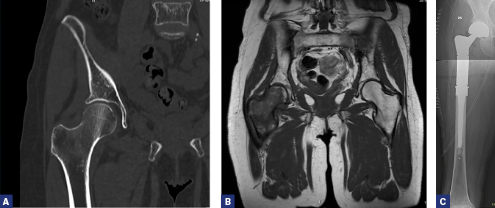

RESEZIONE EN-BLOC

Questa tecnica è particolarmente indicata per lesioni ossee isolate (Fig. 1 a-c) o oligometastatiche in segmenti scheletrici facilmente ricostruibili, offrendo la possibilità di eradicazione locale completa e miglioramento significativo della prognosi a lungo termine, come dimostrato in studi che confrontano la metastasectomia con la sola terapia sistemica23. Trovano una indicazione anche le localizzaizoni estese alla metaepifisi. La ricostruzione con megaprotesi, con fittoni cementati, offre una stabilità superiore e riduce i tassi di reintervento per fallimento dell’impianto, specialmente per le metastasi del femore prossimale o dell’omero25.